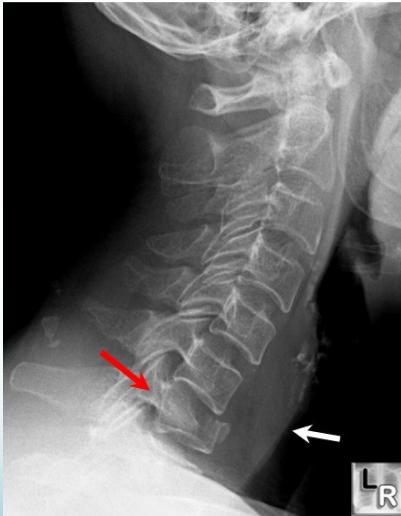

Cervical Burst Fracture

- Axial compression

- Diving

- Unstable

- Neurological injury

Fracture-Dislocation

- Flexion-Rotation

- Articular facets ride forwards over facets below

- Usually with fracture of articular mass

- Unilateral facet: stable

- Displacement < 25% of vertebral body width

- Bilateral facet: Unstable

- Displacement > 25% of vertebral body width